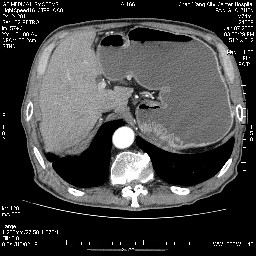

女,74岁,呕吐10余日

肝胰壶腹占位,考虑-壶腹癌!

胃体部粘膜不规则增厚,胃肠造影也显示充盈缺损-胃溃疡?胃癌?

病变主要位于钩突(癌)。如是壶腹部,肝内外胆管扩张明显。

十二指肠降段扩张,水平段狭窄成鼠尾状,肠壁明显增厚,胰腺勾突增大成不均匀强化,其内可见低密度区,胆囊增大,1十二指肠水平段腺癌侵犯胰腺勾突可能大,2胰腺癌侵犯十二指肠(只有胆囊增大没有肝内外胆管扩张不好解释)代除外.

上消化道造影见十二指肠结节状充盈缺损,ct增强十二指肠壁局限性增厚并强化,考虑十二指肠壶腹癌?

十二指肠降段扩张,水平段狭窄成鼠尾状,肠壁明显增厚,胰腺勾突增大成不均匀强化,其内可见低密度区,胆囊增大,1十二指肠水平段腺癌侵犯胰腺勾突可能大,2胰腺癌侵犯十二指肠 。

今日手术结果:胰腺钩突癌侵犯十二直肠,腹腔淋巴结转移.